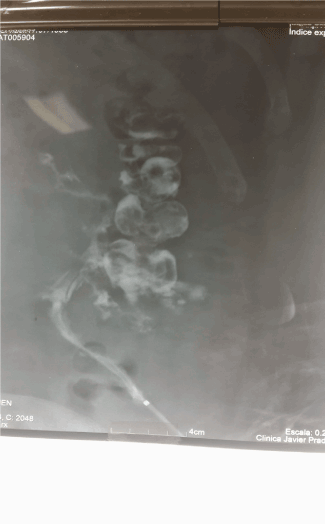

The fistula was treated once a week for 8 weeks. The healing was monitored by a sonogram. With the skin now closed, using a contrast dye was not practical. Initially secretion from the fistula was about 50 cc every four to five days and as the treatment began the outflow reduced until the wound completely healed. The patient had been advised to have major surgery involving a hemicolectomy and a likely colostomy with closure of the second colon.

Figure 3: Ecografia De Fistula Ecografia Post Tratamiento

Figure 4: Paciente Tratado Con 8 Sesiones De Ondas De Choque De Alta Energia Con Equipo Medico